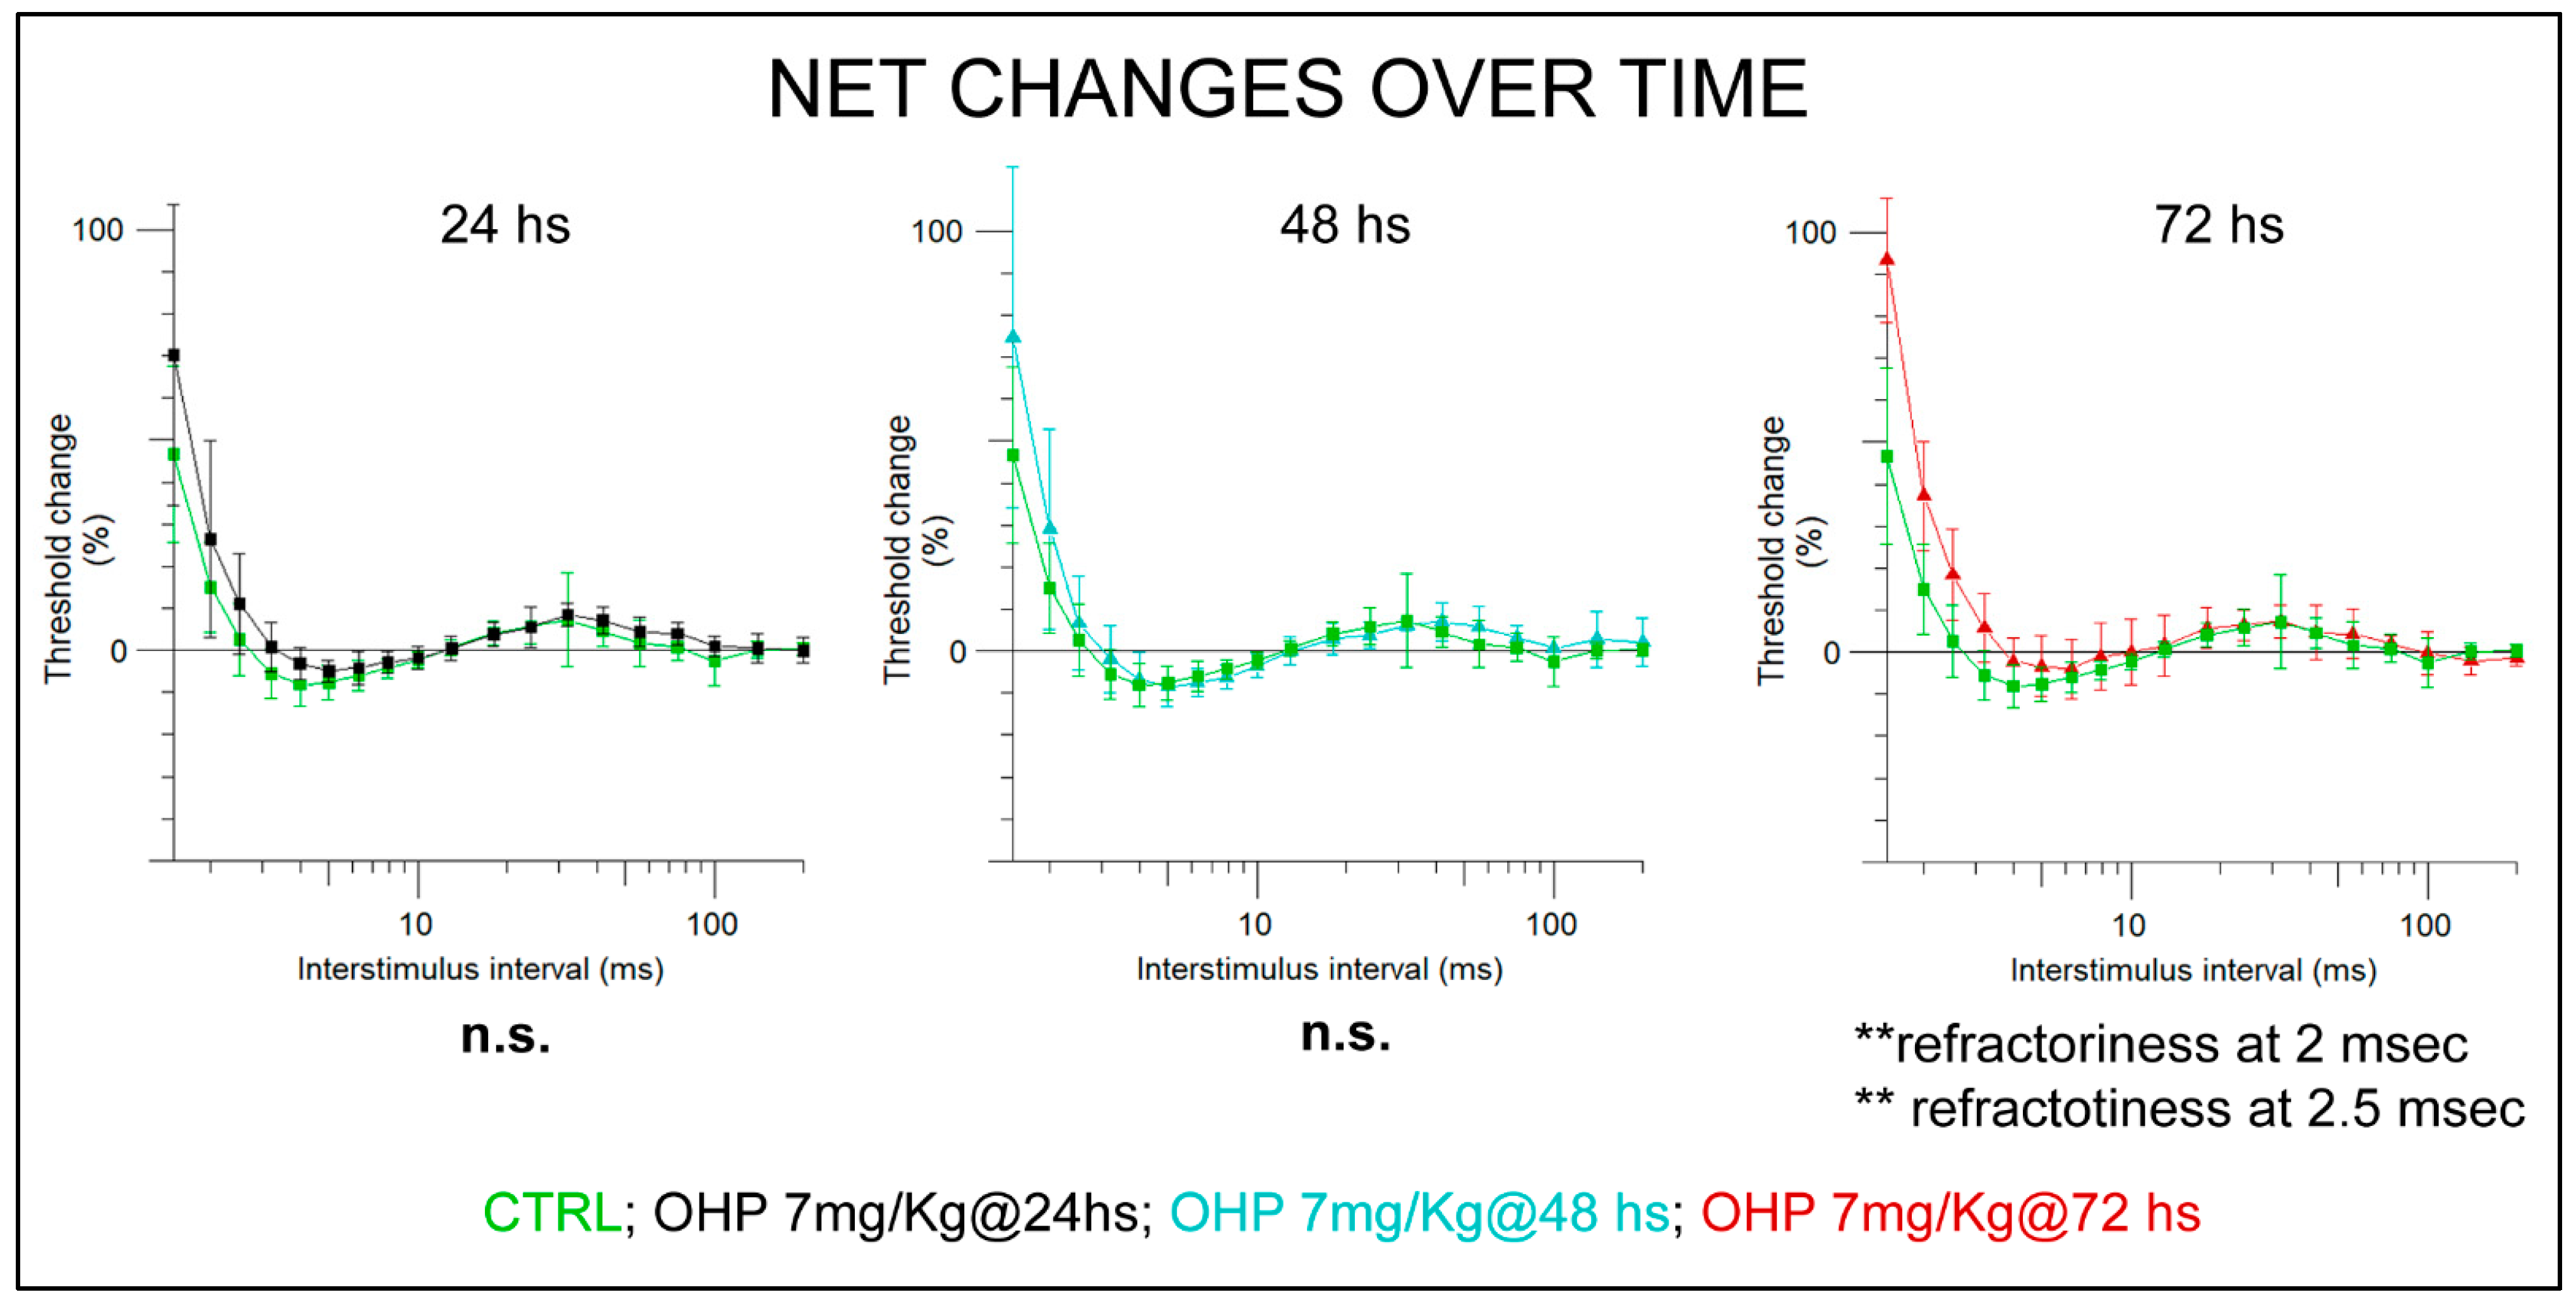

2.2. In Vivo Observations

2.2.1. NET after the 1st Administration